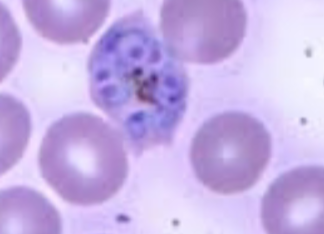

Plasmodium vivax

Plasmodium vivax